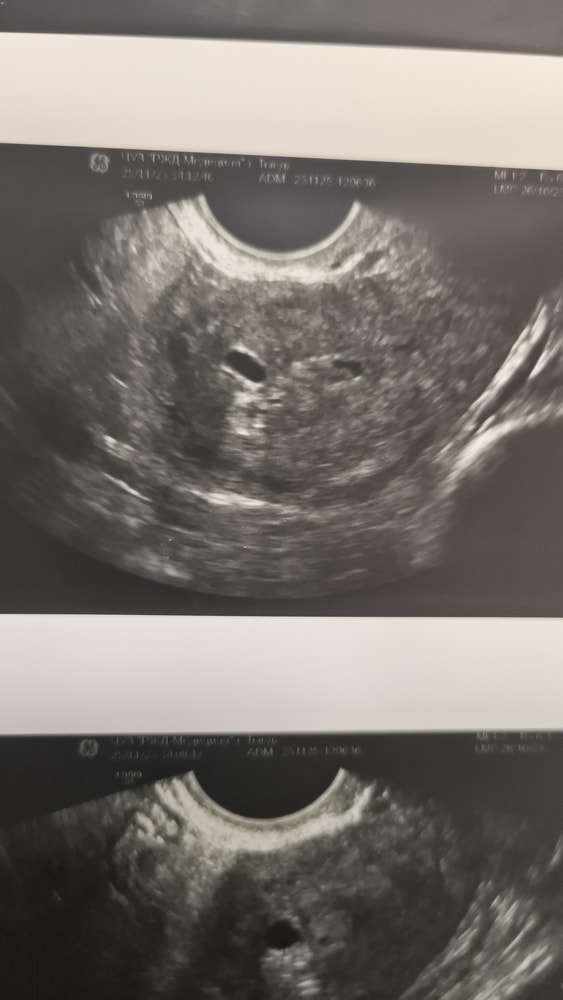

Маруся, маленький уже в матке Изображение

Диана , только что с узи, толь пя, угроза выкидыша

Женечка , только с узи пя в матке, угроза выкидыша Изображение

Наталия Алиева, спасибо большое. Все препараты принимаю. Экстренно на узи увидела пя в матке 4,5 мм, думала не увидят. По месячным 4 н 2 д. Уже радует, что маточная.